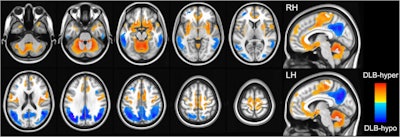

DLB-hypo (hypometabolic changes in dementia with Lewy bodies) was characterized by relatively reduced bilateral metabolic activity (color-coded blue) in the bilateral parietal, temporal, and occipital cortices, while DLB-hyper (hypermetabolic changes in dementia with Lewy bodies) showed relatively increased metabolic activity (color-coded red) in the cerebellum, bilateral sensorimotor, orbitofrontal, insular, and parahippocampal cortices, bilateral putamen, globus pallidum, hippocampus, and amygdala. Image courtesy of npj Parkinson’s Disease.

According to the findings, DLB-hypo was associated with language, visuospatial, visual memory, and frontal/executive functions, while DLB-hyper was responsible for attention and verbal memory. In addition, a linear mixed model showed that DLB-hypo was associated with longitudinal cognitive outcomes, regardless of cognitive status, and DLB-hyper contributed to cognitive decline only in patients with mild cognitive decline, they wrote.